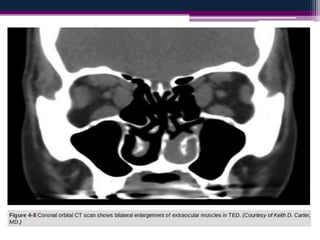

CT shows muscle enlargement

in thyroid eye disease. (A) Axial

view; (B) coronal view – note

sparing of the right lateral

rectus muscle; (C) coronal view

shows crowding at the orbital

apex.

(Courtesy of N Sibtain – figs A and B; J

Nerad, K Carter and M Alford, from

‘Oculoplastic and Reconstructive

Surgery’, in Rapid Diagnosis in

Ophthalmology, Mosby 2008 – fig. C)

Keep in yourmind…. • The inferior rectus is the most commonly involved muscle followed by medial rectus and superior rectus.

CT shows muscleenlargement in thyroid eye disease. (A) Axial view; (B) coronal view – note sparing of the right lateral rectus muscle; (C) coronal view shows crowding at the orbital apex. (Courtesy of N Sibtain – figs A and B; J Nerad, K Carter and M Alford, from ‘Oculoplastic and Reconstructive Surgery’, in Rapid Diagnosis in Ophthalmology, Mosby 2008 – fig. C)